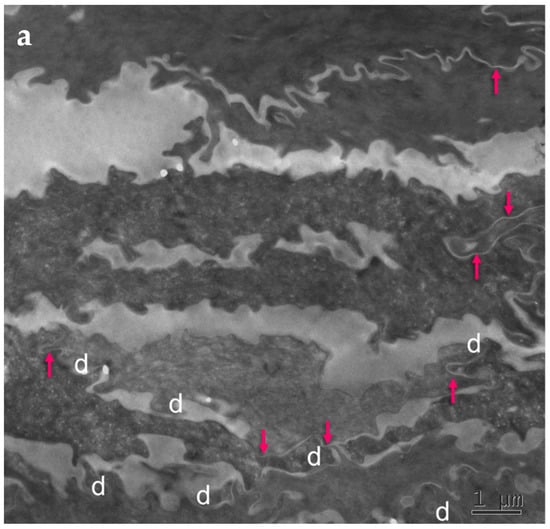

Detailed ultrastructural observations confirmed that TJ-derived points of contact persist in the SC (Figure 1) and can be quantified (Table 1).

Figure 1.

Subdivision of the extracellular space of SC into separate compartments, (a) indicated in different colors; (b) apical-lateral TJ remnants (arrows) intercalating corneodesmosomes (d) may be quantified; (c) an example of “closed” and “open” apical-lateral contacts between the three SC 2 corneocytes. TJ-derived fusions of corneocyte envelopes seal the extracellular space (*). Bar in (a) = 1 µm; in (b,c) = 200 nm.

Ultrastructural features observed in the SC of PSD include paucity of corneodesmosomes (d) that rapidly disappear from the lower parts of the horny layer, as seen in (a), and upregulation of expression of TJ-derived intercorneocyte “fusions” (arrows). (b) In the upper SC, the remaining corneodesmosomes (d) are often found in the proximity of the TJ-derived riveting structures (arrows). Bars = 1 µm in (a); 0.5 µm in (b).